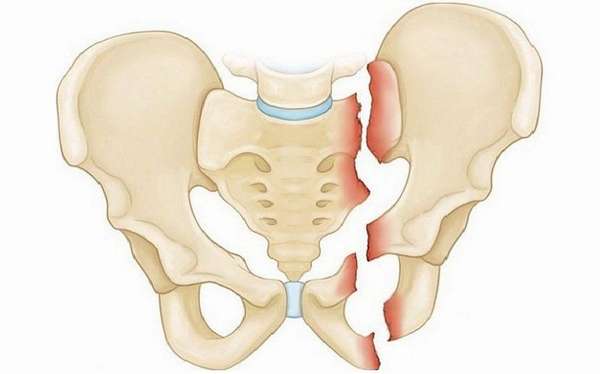

Односторонний перелом седалищной и лонной костей таза

Двусторонние переломы лонной и седалищной костей